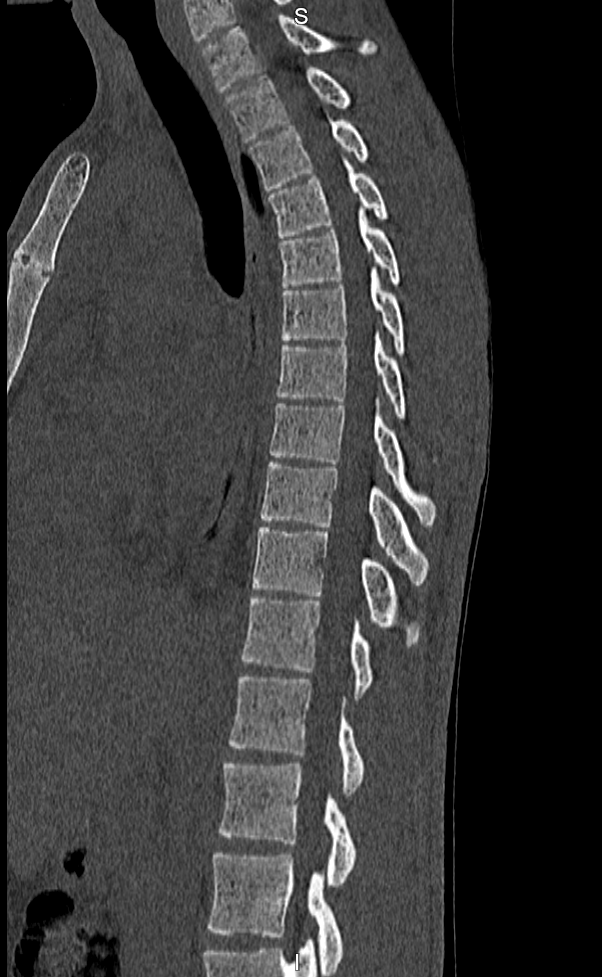

A tomografia computadorizada de coluna é um exame de imagem de alta qualidade e nitidez, que proporciona a identificação de várias patologias que atingem a área da coluna vertebral, como espondilose (artrose na coluna), estenose vertebral (aperto na coluna), espondilolistese (deslizamentos vertebrais), traumas e outros. A ressonância apresenta sensibilidade maior para detectar hérnias. Contudo, nos casos de trauma, a tomografia computadorizada é um excelente método de imagem.